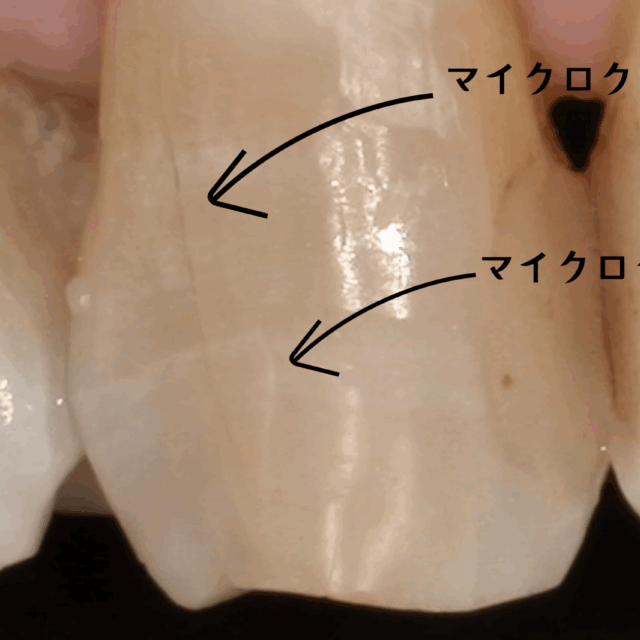

必須条件2:歯科用顕微鏡(マイクロスコープ)

コーティング法は、ミクロン単位の精度が要求される、非常に繊細な治療です。肉眼では、どれだけ優れた歯科医師でも、経験と勘に頼らざるを得ない部分が出てきます。

しかし、歯科用顕微鏡(マイクロスコープ)を使えば、視野を最大で20倍以上にまで拡大できます。これにより、

- 虫歯の取り残しを確実に防ぐ

- 肉眼では見つけられないようなむし歯をしっかりと取り除くことができる

- 健康な歯を削りすぎることを防ぐ

- 肉眼では見えない微細な亀裂や段差を見つけ出す

- コーティング剤を、本当に隙間なく歯の表面に塗り広げられているかを確認する

といったことが可能になります。マイクロスコープを使用しないと、完璧なコーティングは難しいでしょう。成功することもあるかもしれませんが、その確実性は著しく低くなってしまうでしょう。

当院、NK dental TOKYOでの虫歯の再発率が非常に低いのも、虫歯治療において、この「ラバーダム防湿」と「マイクロスコープ」を用いた精密なコーティング法を徹底しているからに他なりません。